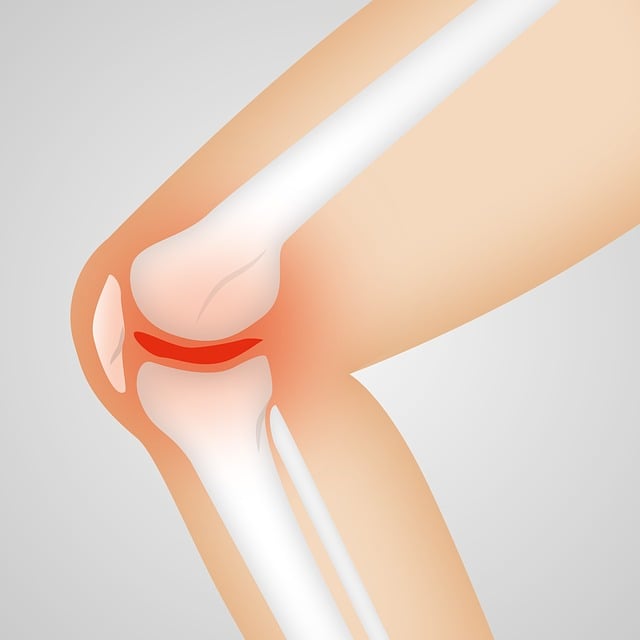

무릎통증 원인, 단순한 통증이 아닌 구조적 문제

무릎 통증의 대표적인 원인은 다음과 같다.

- 퇴행성 관절염: 연골이 닳아 관절 간 마찰이 증가하면서 통증 유발. 50대 이후 여성에게 흔하다.

- 반월상 연골 손상: 스포츠나 외부 충격으로 발생하며, 무릎이 ‘잠기는 느낌’과 함께 통증이 나타난다.

- 십자인대 파열: 격한 운동 중 무릎이 꺾이거나 돌아가면서 발생. 부기와 관절 불안정성이 동반된다.

- 비만: 무릎에 지속적인 체중 압력이 가해져 통증 유발

- 자세 불균형: 양반다리, 쪼그려 앉기, 무릎 꿇는 자세 등은 연골 마모를 가속화한다.

- 체온 저하 및 혈액순환 문제: 겨울철 유독 심한 무릎 통증은 혈류 문제에서 기인하기도 한다.